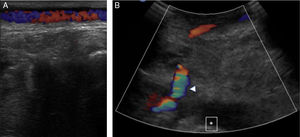

A male, 67 years of age, obese, with high blood pressure and dyslipidemia presented at the emergency department due to pain, cold and functional impairment of his lower left limb of 24-h onset. During anamnesis, the patient stated he had had a chronic intermittent pain in his left knee for a long time. A previous simple knee X-ray showed an osteochondroma (Fig. 1). The patient presented with a femoral pulse but with no popliteal and distal pulses. Artery examination was normal in the contralateral extremity. A CT angiogram was requested for the lower limbs which showed thrombosis of the popliteal artery adjacent to the osteochondroma (Figs. 2 and 3). We decided to perform in situ revascularization with femoro-popliteal saphenous vein graft (Fig. 4) avoiding the tunneling technique for anatomical positioning. To date, after 3 years of follow-up with eco-Doppler, the bypass continues maintaining permeability with ankle-arm index of 0.9, and no signs of popliteal vein injury.

Osteochondroma is the most common pseudotumoral bone lesion. The radiologic pathognomonic characteristic of this tumor is the cortical and medullar continuity of the lesions with the bone from which they protrude.1 They may be single or multiple.2 Some of the most common complications are the presence of bone deformity, fractures,1 vascular compromise3 and neurological compromise,4 formation of a bursa5 and malignant degeneration.6 Diagnosis may be made with an X-ray, although other imaging methods such as a scan, CT and MR may be used in suspected cases when symptoms occur or are in unusual locations.1 Vascular compromise may be caused by displacement of blood vessels (arteries and veins), by stenosis, occlusion and the formation of pseudoaneurisms, with the latter being more frequent at knee level,7 involving the popliteal artery or being presented as arterial thrombosis,8,9 as in this clinical case. Its presentation as thoracic outlet syndrome in the case of rib lesions has been described.10